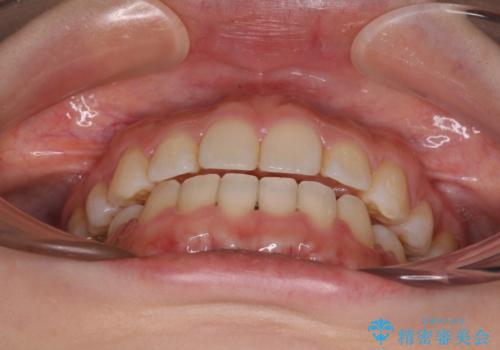

口が閉じられない ワイヤー装置による矯正治療

- 前歯が突出しているために口が閉じられないとのことで来院された患者様です。

上下ともに顎が小さく、歯列が前方に突き出していたため、上下左右の第一小臼歯4本を抜歯し、口元の突出感を改善していくこととしました。